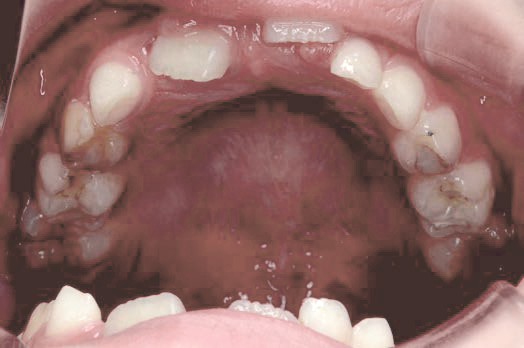

Before

After

上あごの成長が少なく、特に前歯のガタガタが目立っていました。口呼吸のクセや飲み込み方に良くないクセが確認されました。

治療を終えて

マイオブレイスとBB1装置で上あごの成長を助け、鼻呼吸や正しい飲み込み方を身につけることで、きれいな歯並びとしっかり噛めるお口に変わっていきました。

姿勢やお口の機能を正しく整えたので、後戻りしない綺麗な歯並びを維持できています。もちろん非抜歯です。

主訴・治療内容 当院と交流のある歯科医師の先生が、ご自身のお子さまの治療を任せてくださいました。

「難しい歯並びでも永久歯を抜かず、全身の健康と顔立ちも考えて治療してくれる」と信頼していただいて治療開始。

治療期間 3年

費用 462,000円(税込)